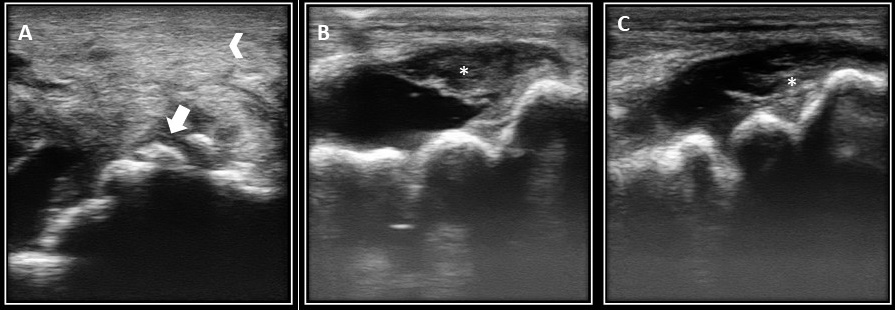

Examen Imagenológico. Se decide hacer una ecografía articular inicial con el fin de evaluar los tejidos blandos, el líquido articular y realizar la técnica de artrocentesis ecoguiada (Figura 1), el ultrasonido articular se realiza con un ecógrafo Emperor medical G30 con una sonda lineal a una frecuencia de 9 MHz, mediante el abordaje lateral de la articulación tarsocrural se observa distensión de la membrana sinovial, con aumento del volumen del líquido sinovial y cambios significativos en su ecogenicidad, ya que se observa hipoecogénico, de ecotextura heterogénea, con presencia de material vegetativo relacionado a bandas de fibrina, las cuales podrían indicar hemorragia intraarticular o hemartrosis, a su vez, se evidencia irregularidad del cartílago articular, sugiriendo un proceso de erosión del mismo.

A. Inicio del caso, se observa aumento del tamaño y de la ecogenicidad de la membrana sinovial con presencia escasa de líquido sinovial (punta de flecha), a su vez, se identifica la presencia de estructuras de radiopacidad mineral compatibles con reacción perióstica. B. (tiempo de evolución de 15 días). C. Tiempo de evolución 4 meses, se evidencia presencia de bandas compatibles con fibrina a nivel del líquido sinovial.

Al realizar el abordaje ecográfico en la porción plantar y medial de la articulación se encuentra aumento severo de tamaño del tejido blando articular con aumento de su ecogenicidad ya que se observó hipoecogénico heterogéneo con mínima cantidad de líquido sinovial, a lo largo de la evolución del caso los hallazgos ecográficos mostraron una disminución marcada del líquido sinovial, con presencia de múltiples estructuras hiperecogénicas de bordes irregulares compatibles con osteofitos, así mismo, el tejido blando aumentó de tamaño y de ecogenicidad.

La ecografía puede indicar hallazgos relacionados con el tejido blando y la superficie perióstica a nivel articular (13). De acuerdo a lo anterior Caron (14), da prioridad a la ecografía con respecto a la radiografía convencional ya que permite la observación de anormalidades en las vainas sinoviales, cápsula articular, membrana sinovial y lesiones intraarticulares (14). Denoix (15), afirma que las indicaciones para la evaluación ecográfica articular incluyen distención por efusión sinovial, aumento de tamaño local, dolor a la manipulación pasiva y hallazgos significativos en la analgesia o anestesia periarticular (15). A pesar de que el ultrasonido se absorbe completamente en la porción cortical del hueso, las características periósticas pueden ser evaluadas, encontrando hallazgos como osteofitos periarticulares, entesófitos, fragmentos osteocondrales e irregularidades de la porción subcondral (14). Lo mencionado anteriormente se relaciona con la evaluación ecográfica del caso actual donde se encontraron hallazgos como aumento del tamaño y la ecogenicidad de la membrana sinovial, marcada disminución del líquido articular, irregularidad del borde perióstico, desprendimiento de fragmentos osteocondrales con presencia de sombra acústica. Durante el seguimiento ecográfico del caso se encontró un aumento progresivo del tejido inflamatorio, la ecogenicidad del mismo aumento drásticamente, a su vez, hubo una marcada disminución del líquido sinovial.